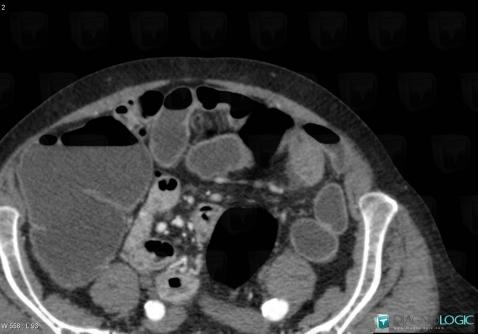

Small bowel adenocarcinoma, Small bowel, CT

Here is the specific information in the key image above:

- Diagnosis Small bowel adenocarcinoma, Location(s) Small bowel, with gamuts Focal thicknening of small bowel wall, Marked thicknening of small bowel wall